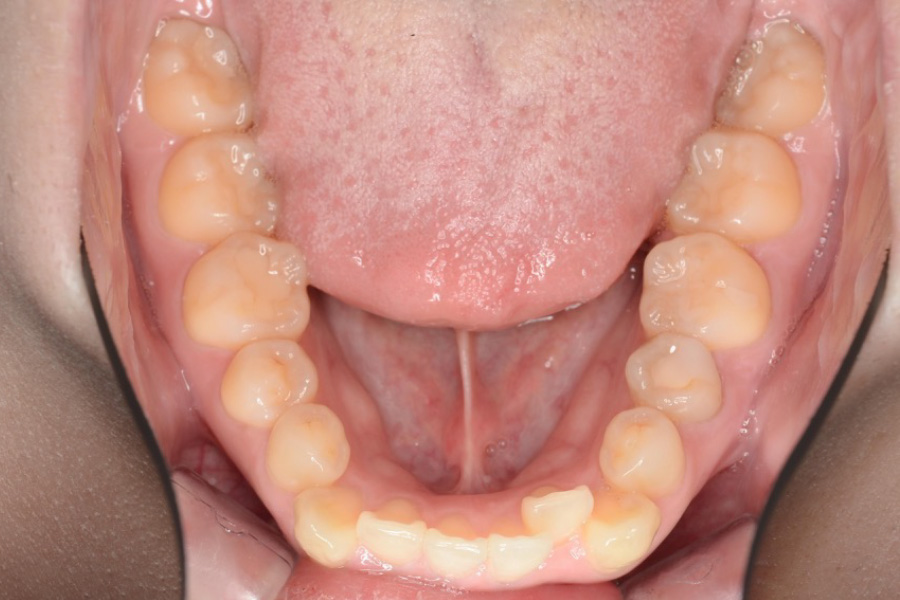

【20代女性】

歯のガタつき、突出感を

インビザライン矯正で治療したケース

治療前

主訴 歯のガタつき、突出感が気になる

治療内容 インビザライン矯正

小臼歯抜歯